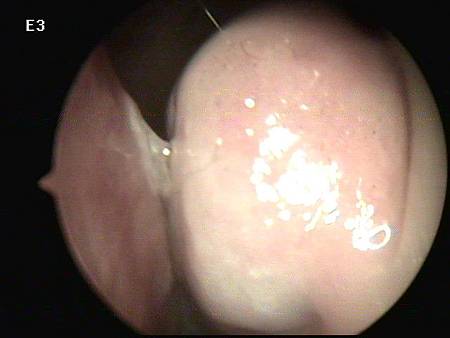

不用多說, 把內視鏡放進鼻子裡一看,

連她自己也嚇一跳!